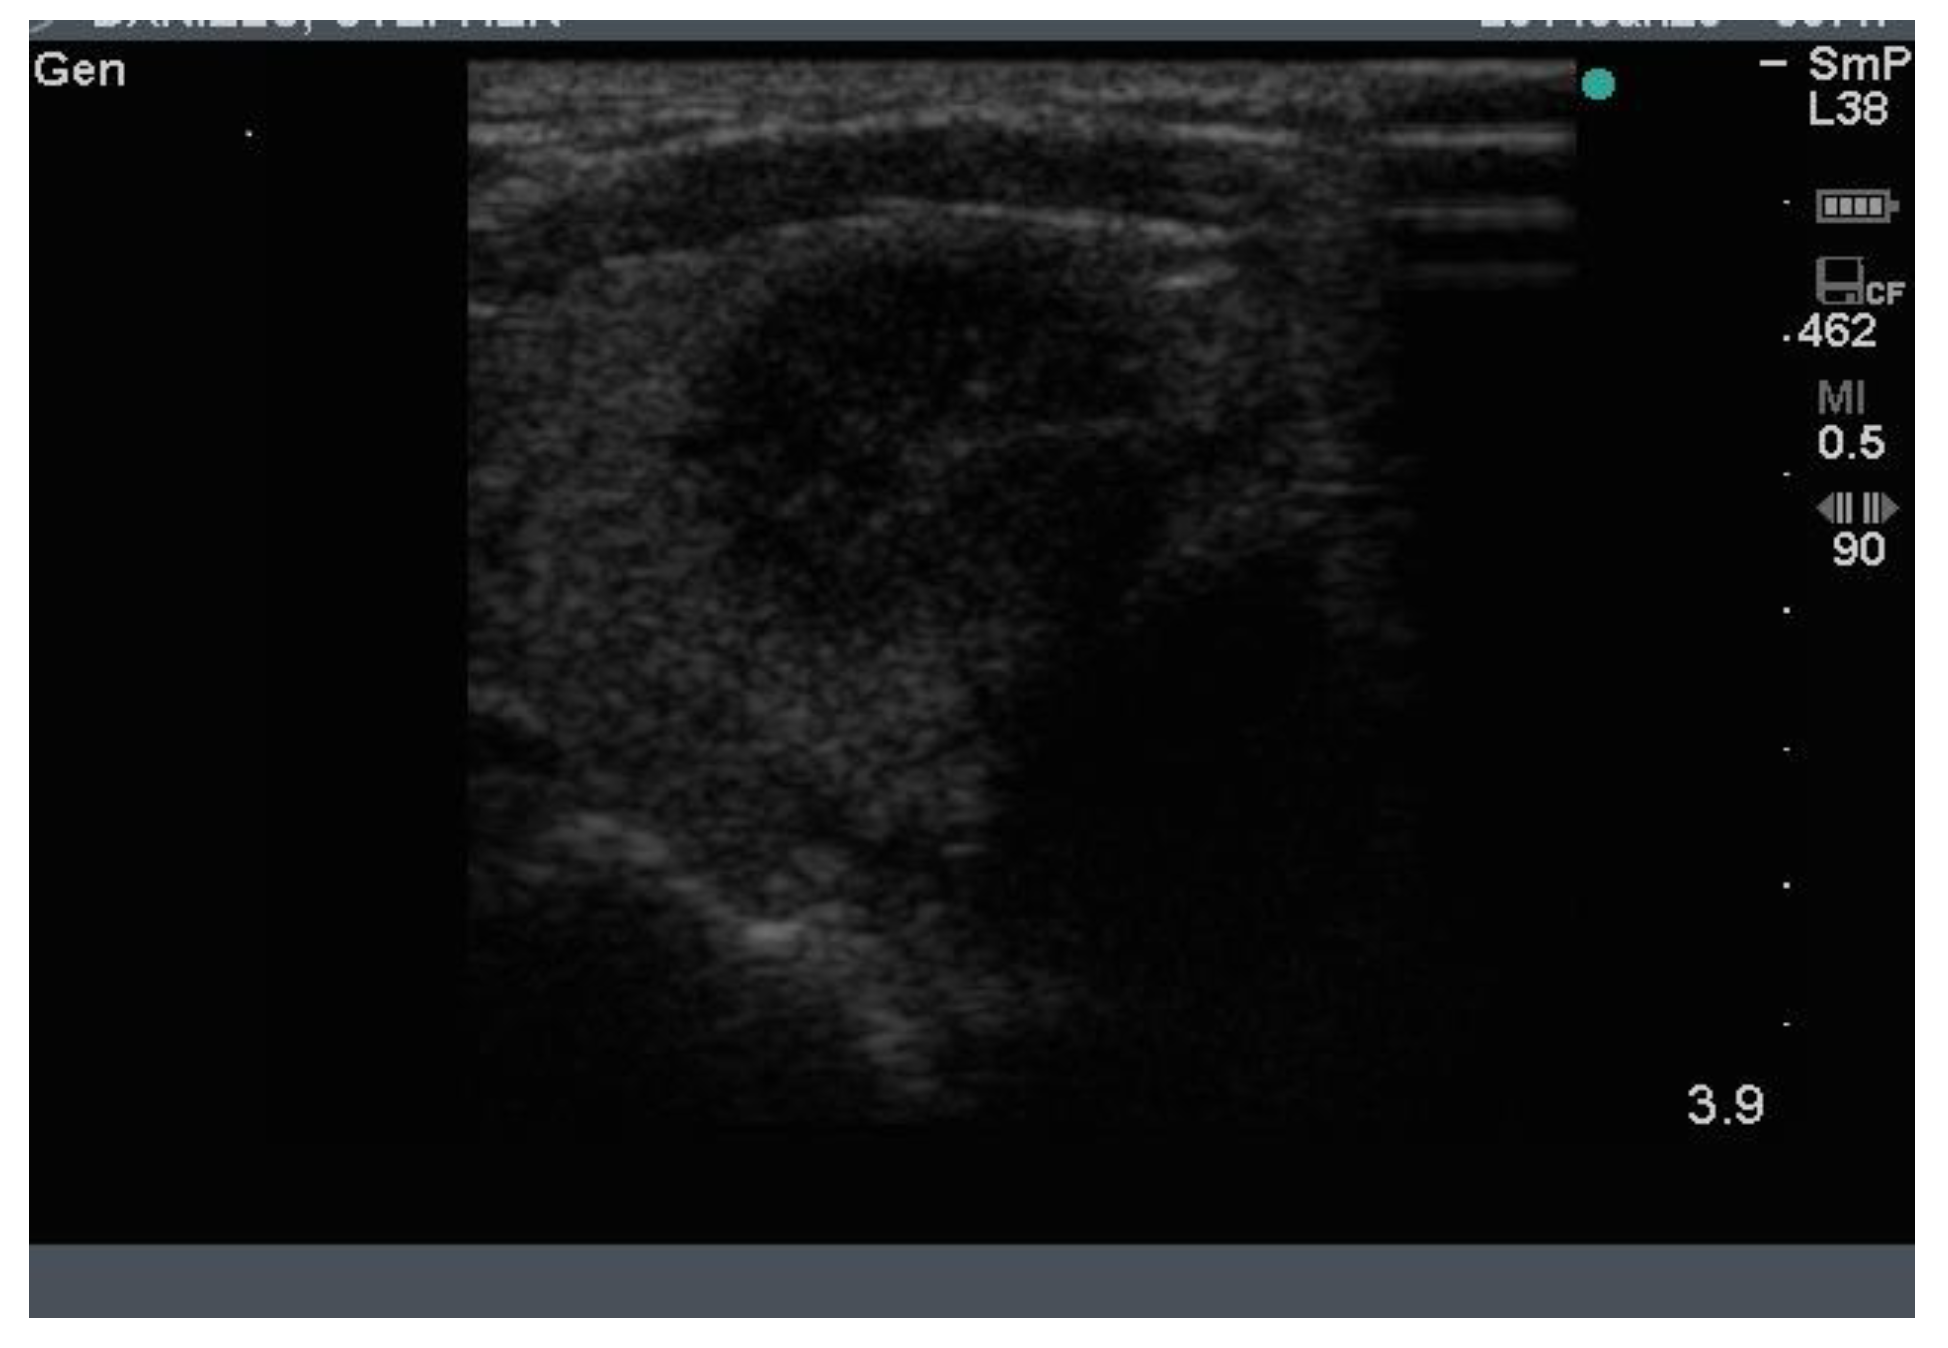

Three examples of papillary thyroid cancer are shown here. Firstly, a large typical papillary cancer with the characteristic microcalcifications is seen in Figure 11.

Figure 11.

Thyroid ultrasound from a patient with confirmed papillary thyroid cancer. The nodule is large (3 cm) and hypoechoic with an indistinct irregular edge and central microcalcifications. The calcifications are softer (less white) than seen above in some benign nodules and larger, around 2–3 mm (arrow). There is no halo. Not seen here, the blood supply was increased in the lesion and there was a feeding vessel on one side of the lesion. Another example of macrocalcifications in papillary thyroid cancer.